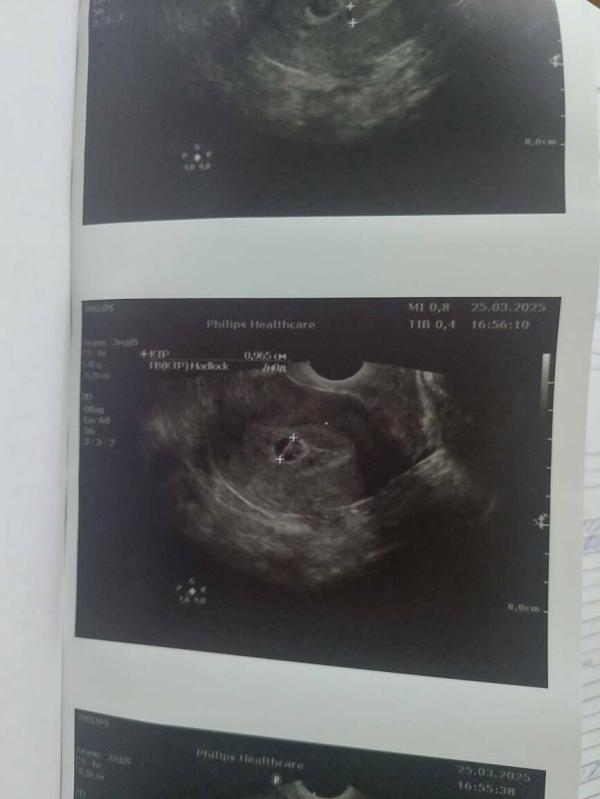

К обеду пошла кровь, я поехала в стационар при приёмке ктр наметили 9.5 мм(3 фото)+отслойка и как то по узи не особо много место ему